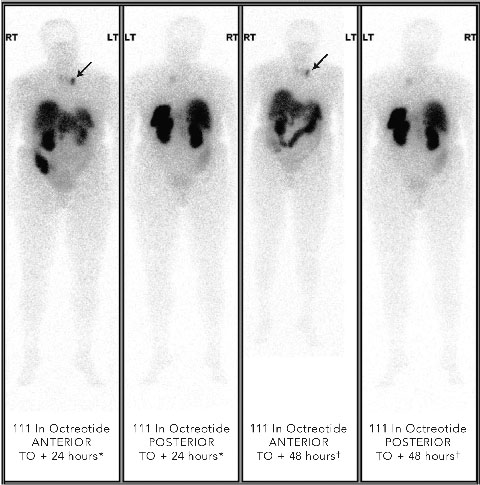

Localisation studies with a 123 I-metaiodobenzylguanidine scan identified increased tracer uptake within both the left adrenal region and left anterior mediastinum. Computed tomography and magnetic resonance imaging (MRI) scans showed large bilateral renal angiomyolipomas (AMLs), a right renal artery aneurysm, a bulky left adrenal gland with no discrete mass lesion, and a 15 mm calcified lesion within the left anterior mediastinum (not related to the sympathetic chain). Results of a positron emission tomography scan were negative. However, an octreotide scan showed mild tracer uptake in the left adrenal region and marked focal uptake within the left anterior mediastinum (Box 2).

2 Octreotide scans of patient with phaeochromocytoma metastasis showing abnormal focal tracer uptake in anterior mediastinum (arrows in anterior views)